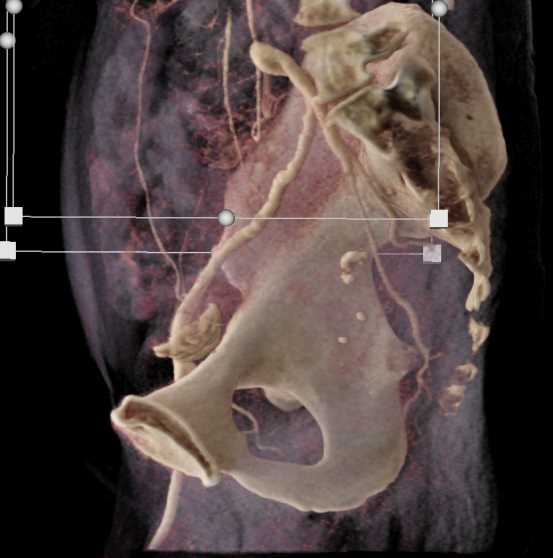

Urachal Carcinoma of the Bladder